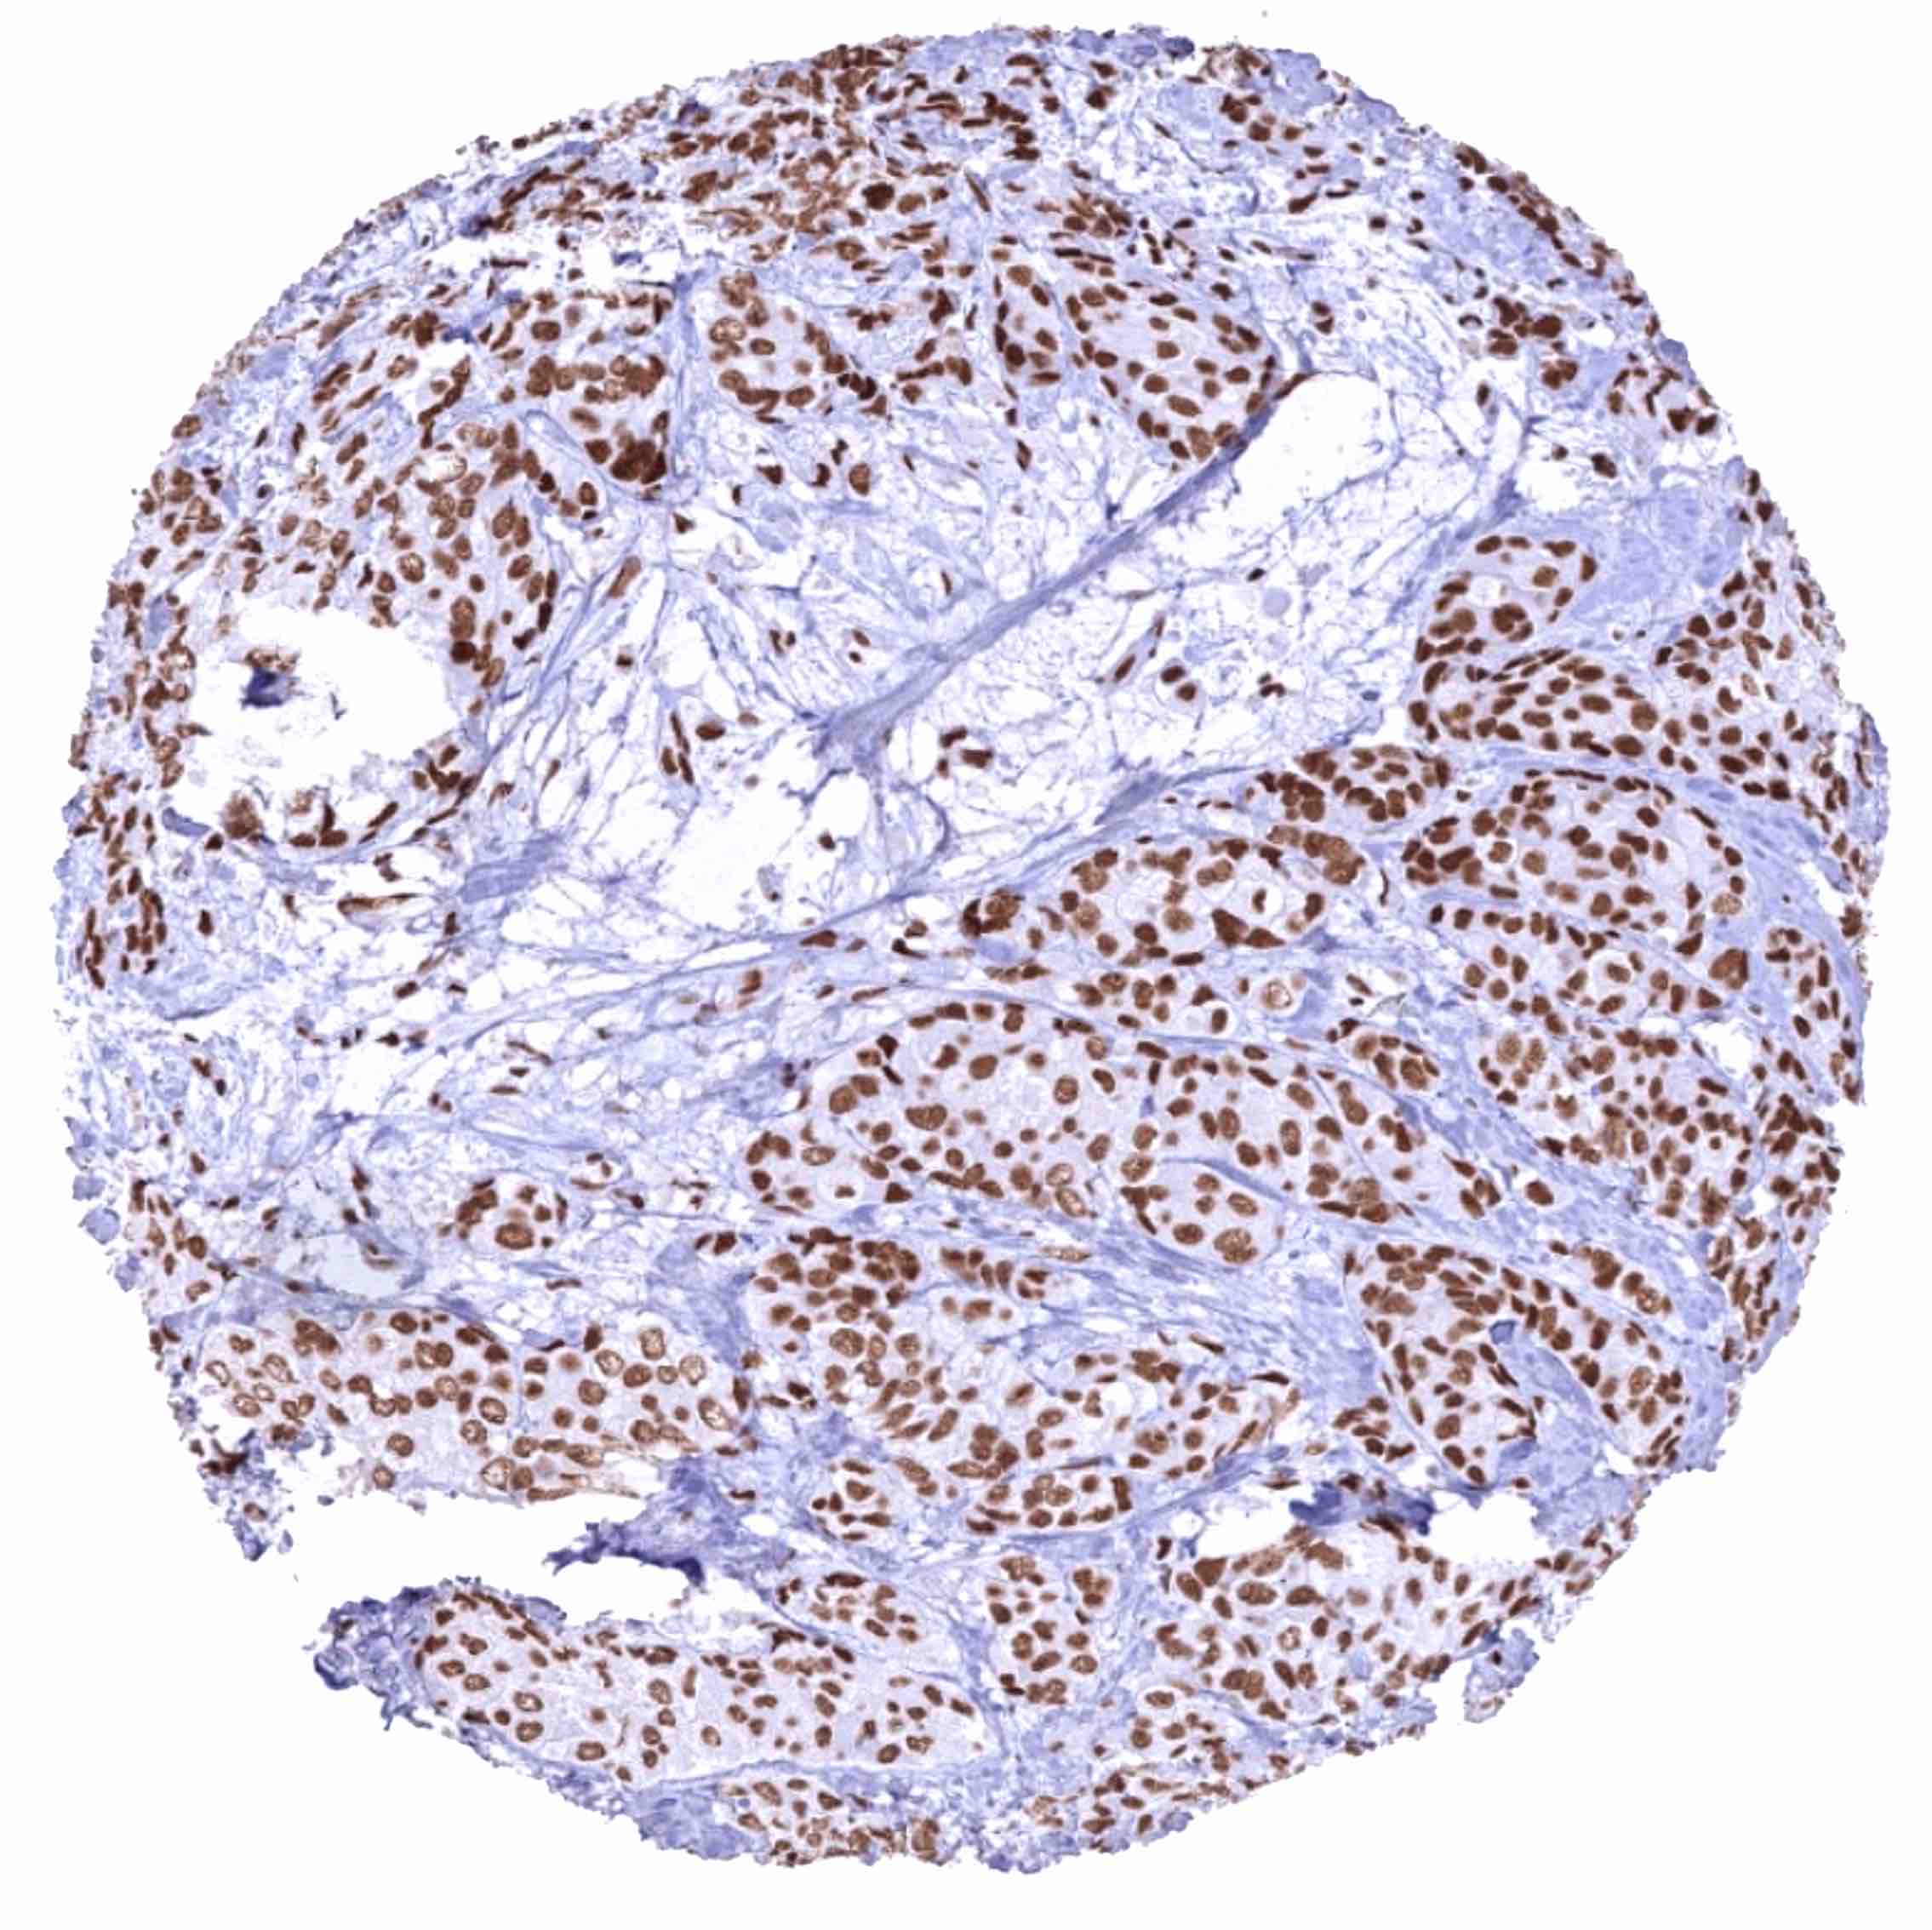

Urinary bladder – Muscle-invasive urothelial carcinoma with intense BRD4 staining of all tumor cells.